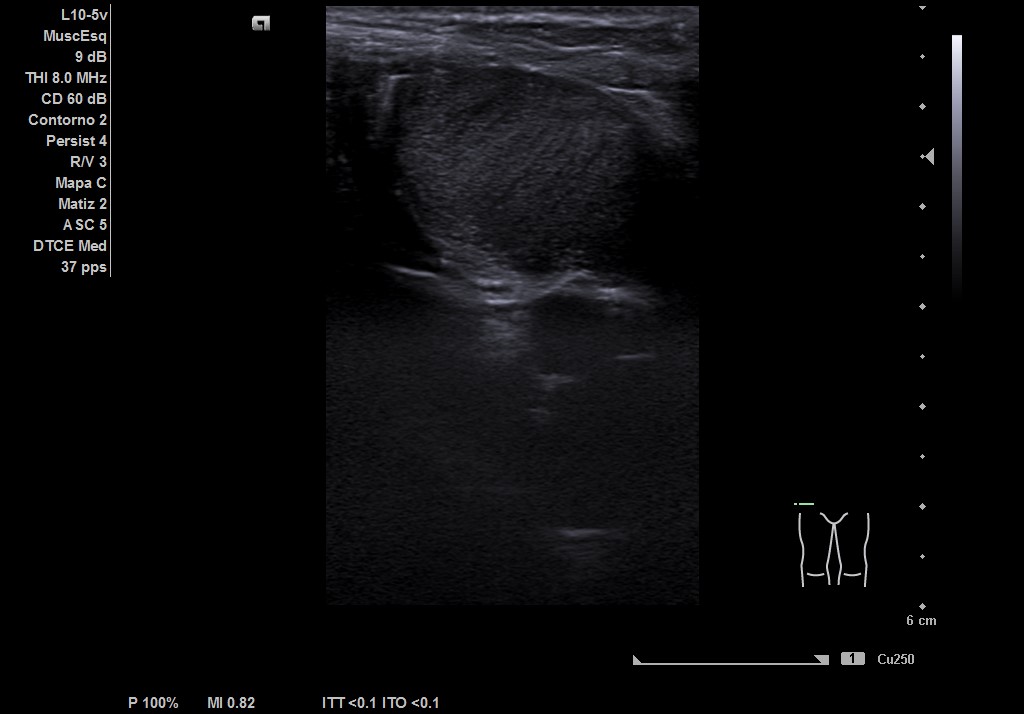

Durante la realización de la prueba, el paciente comenta que en ocasiones no encuentra el testículo derecho. Por lo que decidimos cambiar a la sonda lineal y explorar planos más superficiales donde observamos el testículo derecho, por encima del ligamento inguinal, en fosa ilíaca derecha con ecoestructura normal, homogénea y vascularización normal.